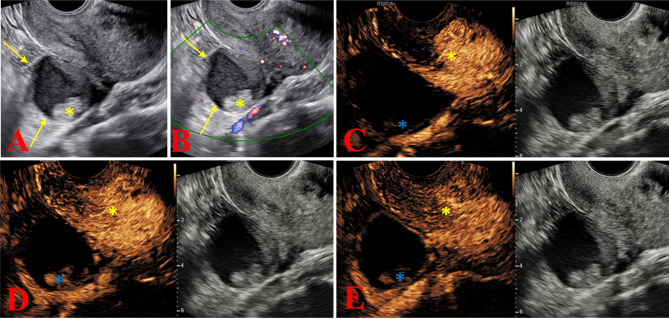

Methods: From January 2018 to August 2021 (the test group) and from September 2021 to September 2022 (the validation group), the data of patients classified as O-RADS US v2022 categories 2 to 5 who underwent adnexal ultrasound examinations were prospectively and continuously collected. In the test group, univariate and multivariate analyses were used to explore the relationship between age, body mass index (BMI), maximum diameter of the lesion, menopausal status, HE4, cancer antigen 125 (CA125), and the characteristics of CEUS and malignant lesions. Selecting independent influencing factors to construct diagnostic model, which was validated in the external validation group and compared with subjective evaluation.

Results: The test group included 563 patients (mean age, 48.7 ± 13.2), and the validation group included 246 patients (mean age, 47.6 ± 12.9). Univariate and multivariate analyses showed that enhancement time, enhancement intensity, dynamic changes, and HE4 were independent influencing factors for predicting adnexal malignant tumors. In the validation group, the sensitivities and specificities of O-RADS US v2022, O-RADS US v2022 + CEUS, O-RADS US v2022 + CEUS + HE4, and subjective assessment were 88.89% and 70.69%, 94.44% and 79.31%, 91.67% and 92.53%, and 93.09% and 89.66% respectively. In addition, the combined diagnostic performance of O-RADS US v2022, CEUS and HE4 (AUC = 0.980) was higher than that of O-RADS US v2022 alone (AUC = 0.876, P < 0.001) and the combination of O-RADS US v2022 + CEUS (AUC = 0.908, P < 0.001), and was comparable to the subjective evaluation (AUC = 0.963, P = 0.192).

Conclusions: The combined diagnostic model of O-RADS US v2022, CEUS and HE4 can improve the specificity of adnexal ultrasound diagnosis without sacrificing sensitivity, and it has high reliability.